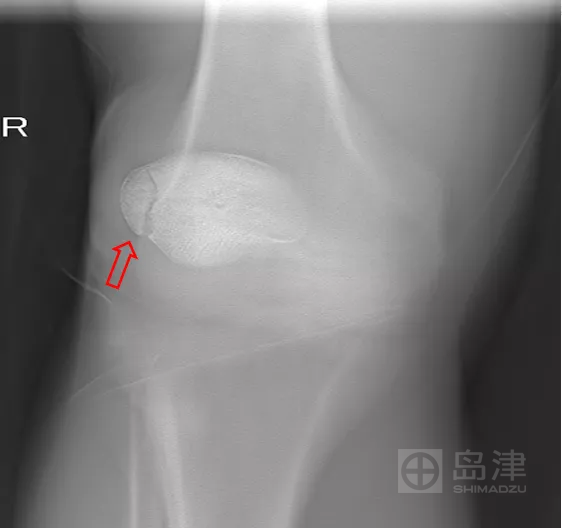

病例三:骨折征象显示

45岁男性,与孩子玩耍时,从一级台阶上蹦下即感右膝疼痛明显,无法行走。

右膝正侧位X线:未见骨折直接及间接征象 。

DTS 显示胫骨平台骨折 。

查 CT MR ,与DTS结果一致。

隐匿性骨折 DR无法发现

右胫骨平台隐匿性骨折

DTS可发现平片无法发现的骨折

CT结果与DTS一致

MRI结果与DTS一致

图像来源:西安市第九医院